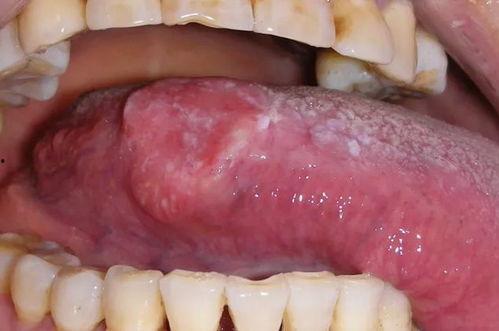

最近是不是觉得嘴巴里有个小火山在喷发?舌头溃疡的滋味,相信我,那可不是什么好受的体验。但是,你知道吗?在这个时候,有一种神奇的食物——凉瓜,竟然可以成为你的救星!是的,你没听错,就是那个绿油油的凉瓜,它竟然能帮你缓解舌头溃疡的痛苦。下面,就让我来给你详细介绍为什么舌头溃疡可以吃凉瓜,以及如何正确地享用它。

你知道吗,舌头溃疡的成因有很多,比如口腔卫生不好、压力大、免疫力下降等等。而凉瓜中的有效成分,如苦瓜素、维生素C等,可以帮助你缓解这些不适。

1. 苦瓜素:这是一种天然的消炎成分,能够有效地抑制口腔溃疡的炎症,减轻疼痛。

2. 维生素C:这种抗氧化剂能够增强你的免疫力,帮助你抵抗病毒和细菌的侵袭,从而减少舌头溃疡的发生。

3. 清热解毒:凉瓜的清热解毒作用可以帮助你清除体内的热毒,从而缓解舌头溃疡的症状。